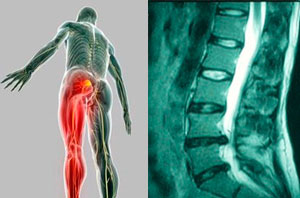

"A principios de marzo, comencé con un dolor muy intenso a la pierna izquierda, el cual, lo había asociado a las hernias lumbares que me habían llevado a terapia a lo largo de 7 años, pero por periodos cortos y logrando un alivio al dolor. Pasaron 3 semanas y a pesar de las inyecciones y pastillas mi dolor fue emporando. Me indicaron que las hernias necesitaban una cirugía, pero recibí información muy diferente de varios médicos; unos me dijeron que no se podían operar las dos hernias solo una, me dijeron que era muy peligroso e inclusive que si me operaban las dos hernias iban a tener que instrumentar mi columna, por lo tanto, estaba en mucha duda respecto a mi operación. Por refencias de unos familiares llegué a conocer al Dr. Carlos Cardenas y muy pacientemente me explico con todos los detalles qué es lo que tenia y cómo es que se tenía que proceder. Me operó y mis molestias han desaparecido y en menos de 1 mes estoy totalmente recuperado. Realmente me alegro mucho de haberlo conocido, ya que me brindo una atención sumamente profesional, correcta y humilde. Me ayudó a comprender cuándo es que se tiene que operar una hernia y cuándo no, con lo cual, obtuve una total confianza en él."

Espondilolistesis

Tengo 62 años, hace 2 años sin causa aparente comencé a sufrir de dolor de espalda bajo frecuente e intenso, y posteriormente se me adormecían, tenía calambres frecuentes y sentía pesadas las piernas. Consulte varias clínicas, hice muchas sesiones de rehabilitación, use corset, etc. sin embargo mis molestias eran cada vez más intensas. Me dijeron que tenía ESPONDILOLISTESIS L4-L5 y que debía operarme, visite varios especialistas pero ninguno me transmitía seguridad y confianza.